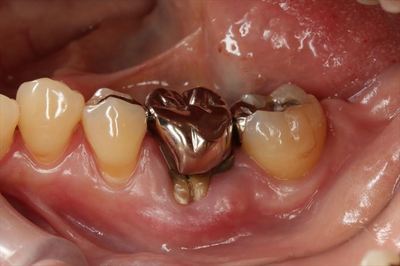

かぶせ物(メタルクラウン)を抜歯鉗子でグリップしてゆっくり動かすと

ほどなくメタルコアから脱離しました。

金属と接していた部分は特徴的な黒い状態になっています。

脱離したメタルコアとメタルクラウンが一体となったものです。

メタルコアの銀合金がとても黒くなっています。